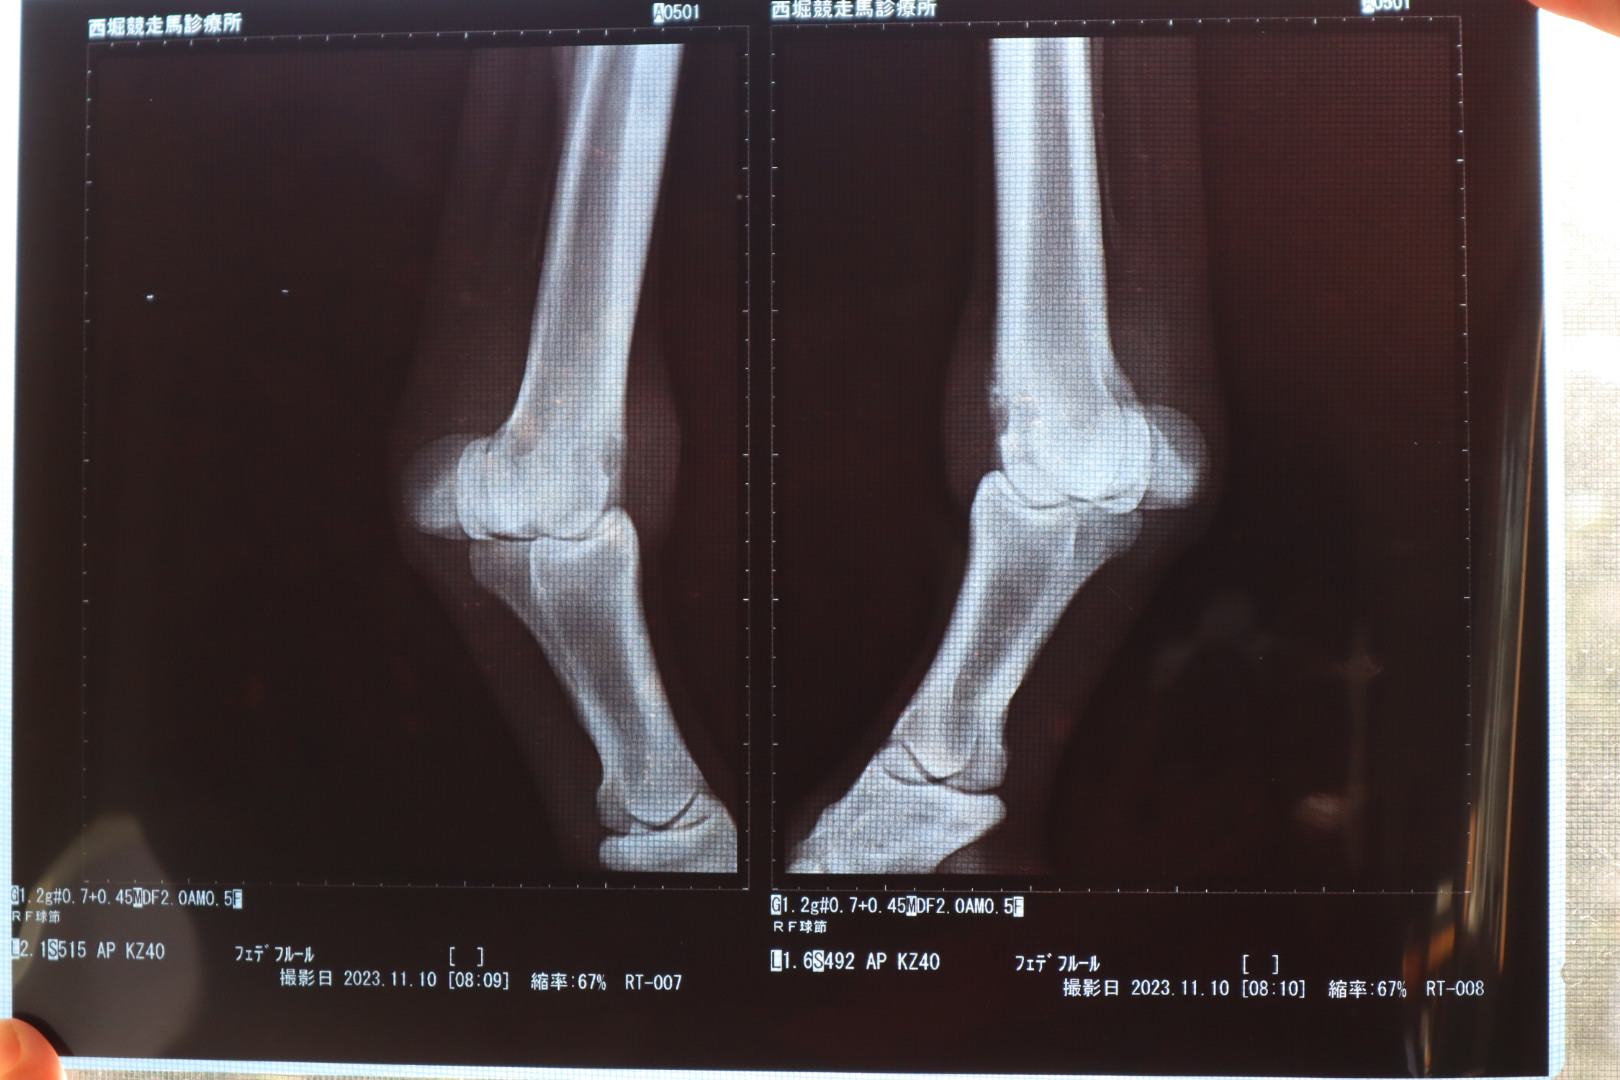

なお、オークション出品に伴い、2023年11月10日にレントゲン撮影を行ったところ、右前球節前面部に僅かに骨膜が確認されています。